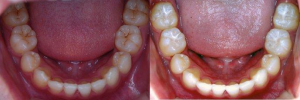

Q什么是“六龄齿”?

A:孩子6岁左右时,在第二乳磨牙后萌出的牙,叫“第一恒磨牙”,因其在6岁左右萌出,习惯称为“六龄齿”或“六龄牙”。

A:六龄齿牙尖多,牙尖与牙尖之间的窝沟多,且又深又窄,容易藏垢纳污,不易清洁,所以龋坏率高。